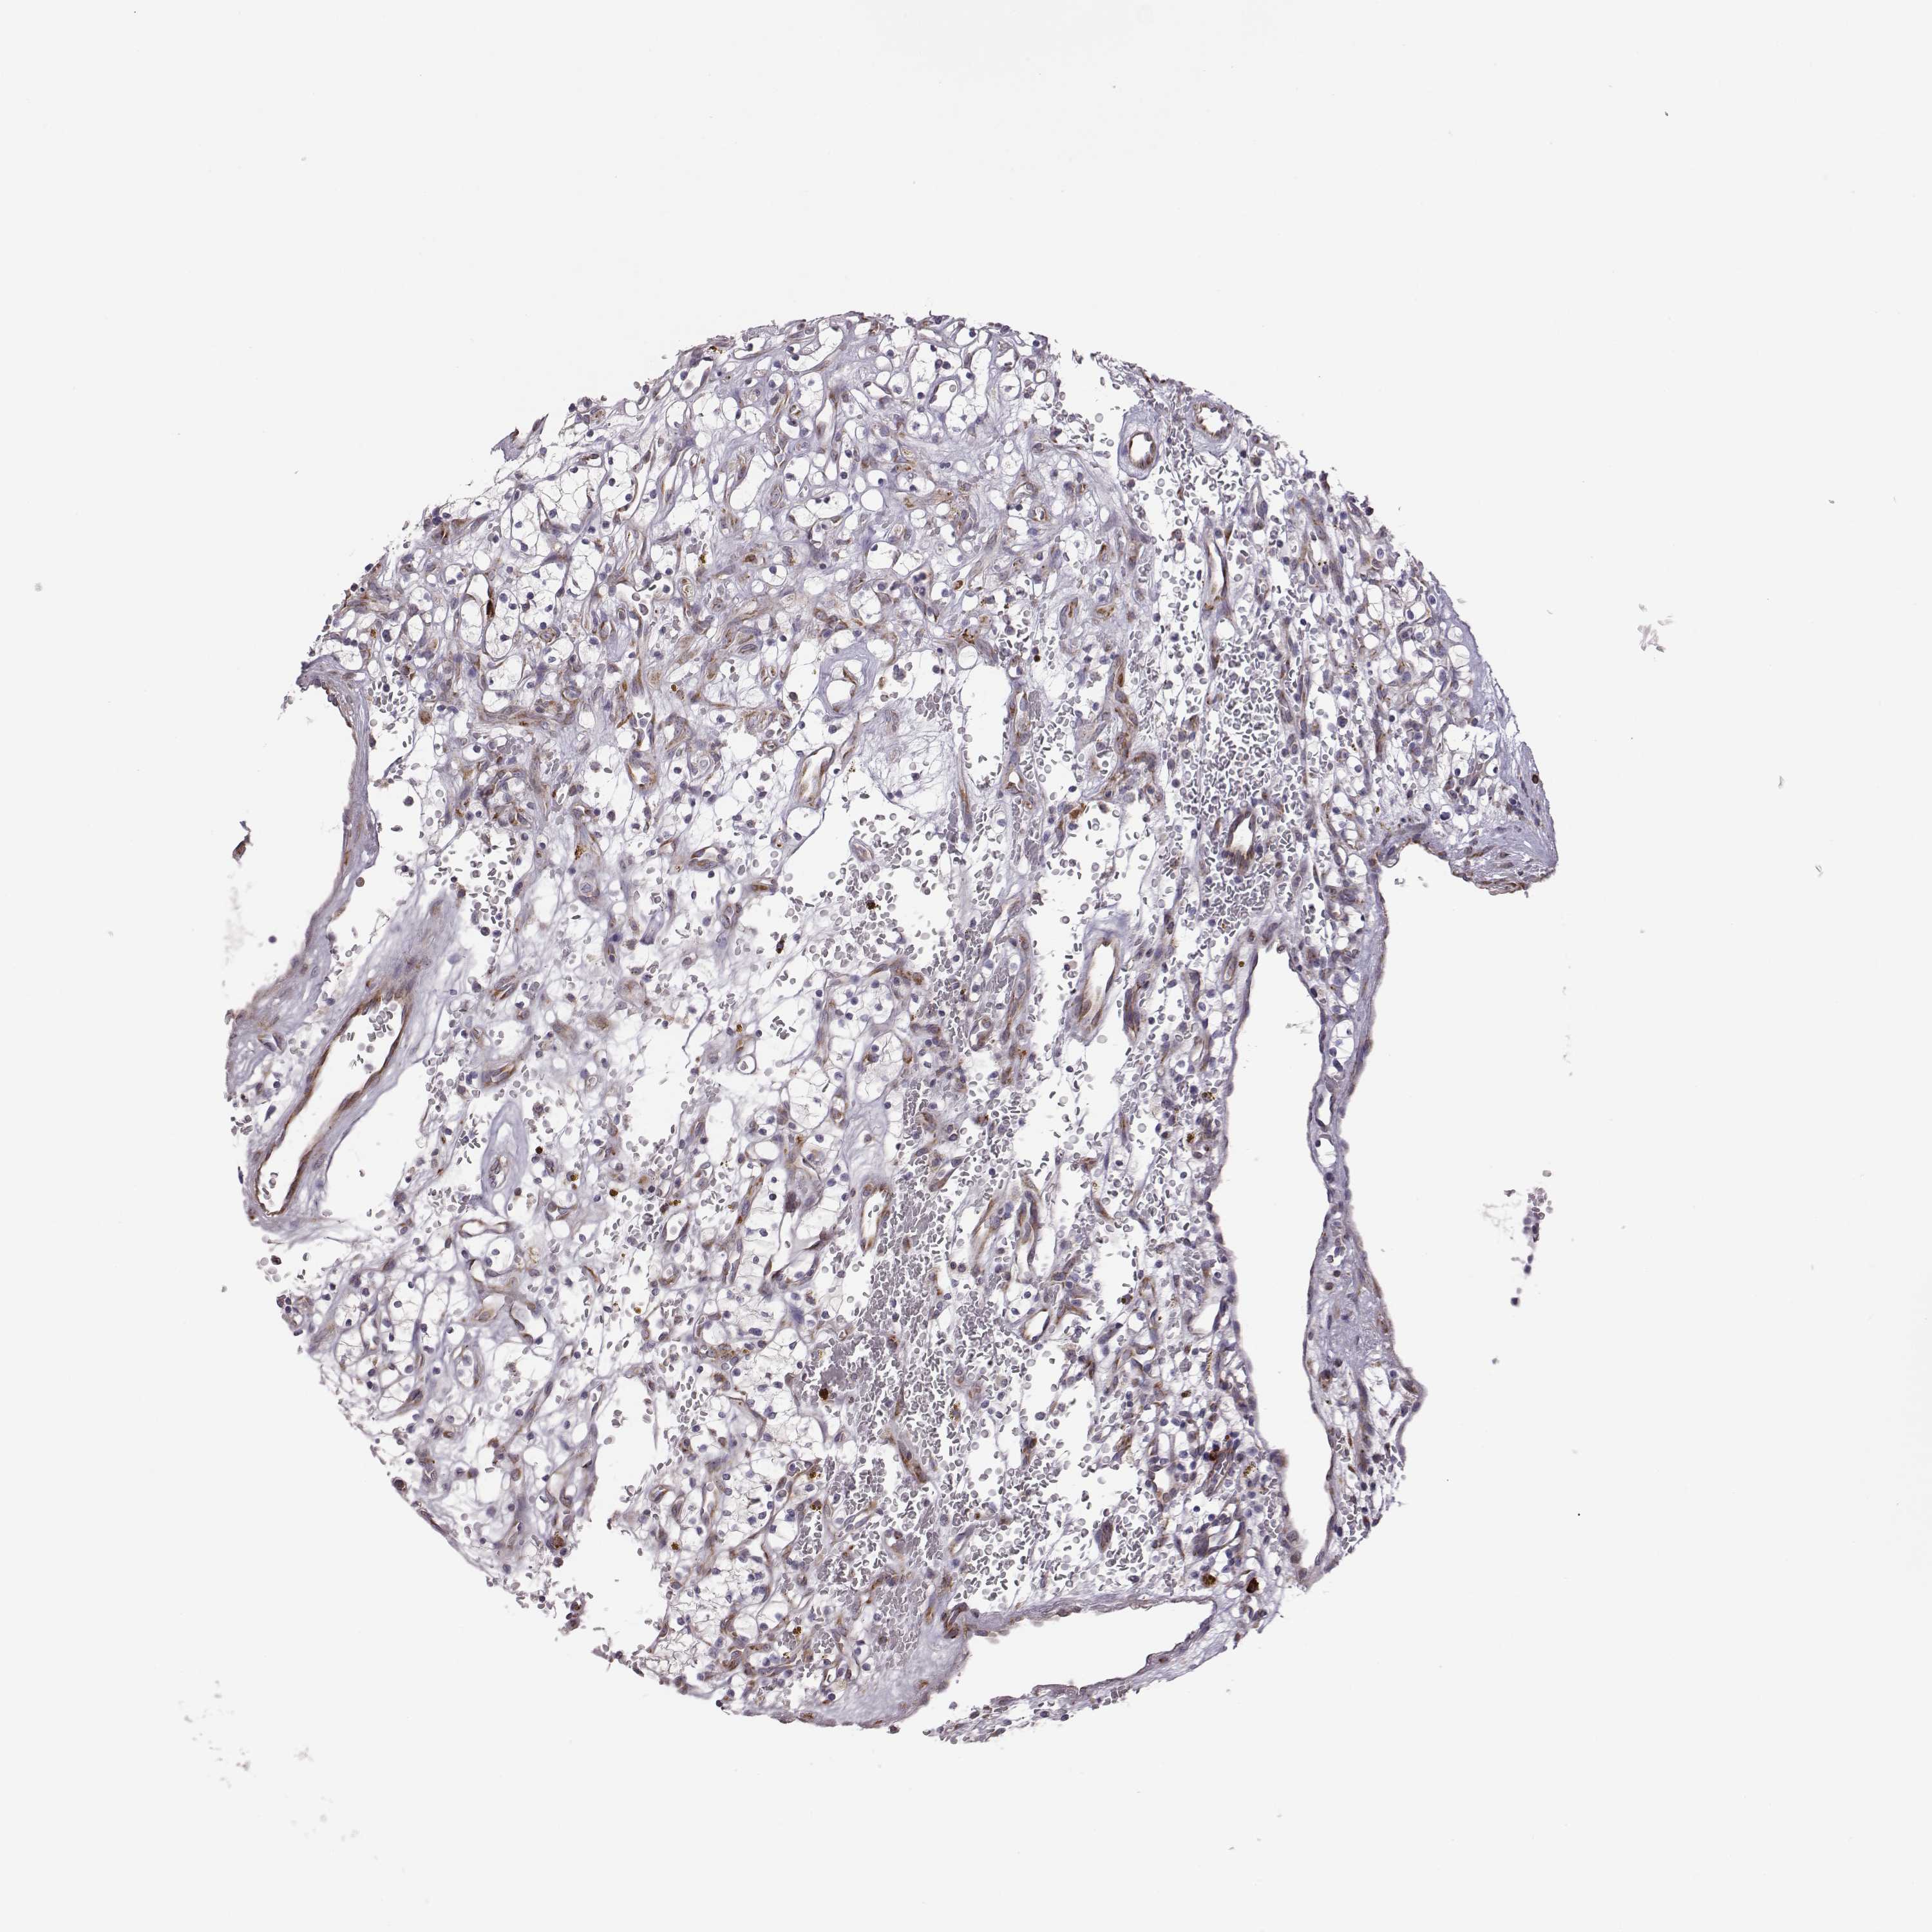

KIDNEY RENAL CLEAR CELL CARCINOMA (VALIDATION) - Interactive survival scatter ploti

The Survival Scatter plot shows the clinical status (i.e. dead or alive) for all individuals in the patient cohort, based on the same data that underlies the corresponding Kaplan-Meier plots. Patients that are alive at last time for follow-up are shown in blue and patients who have died during the study are shown in red.

SELENOI is not prognostic in Kidney Renal Clear Cell Carcinoma (validation)

: 6.93

Average pTPM 9.8

Number of samples 100